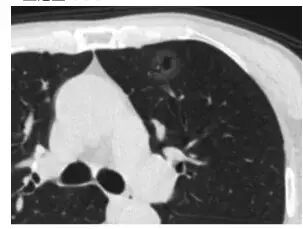

3. 隐球菌感染(「肺里面长蘑菇了」)

这个也像 GGO,还有一个小空洞